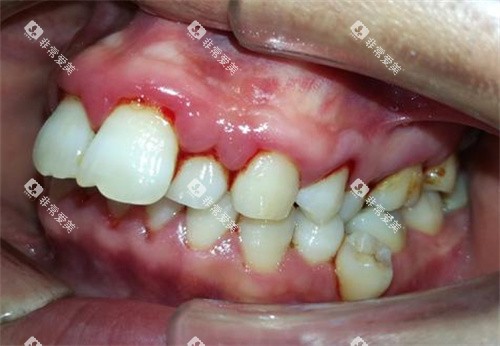

补牙的收费根据补牙材料和龋坏程度而定。

一般来说,树脂补牙的费用在几百元到上千元不等。

如果龋坏程度较浅,只需要简单的补牙,费用相对较低;如果龋坏已经累及牙髓,需要靠前行根管治疗,再进行补牙,费用会相应增加。